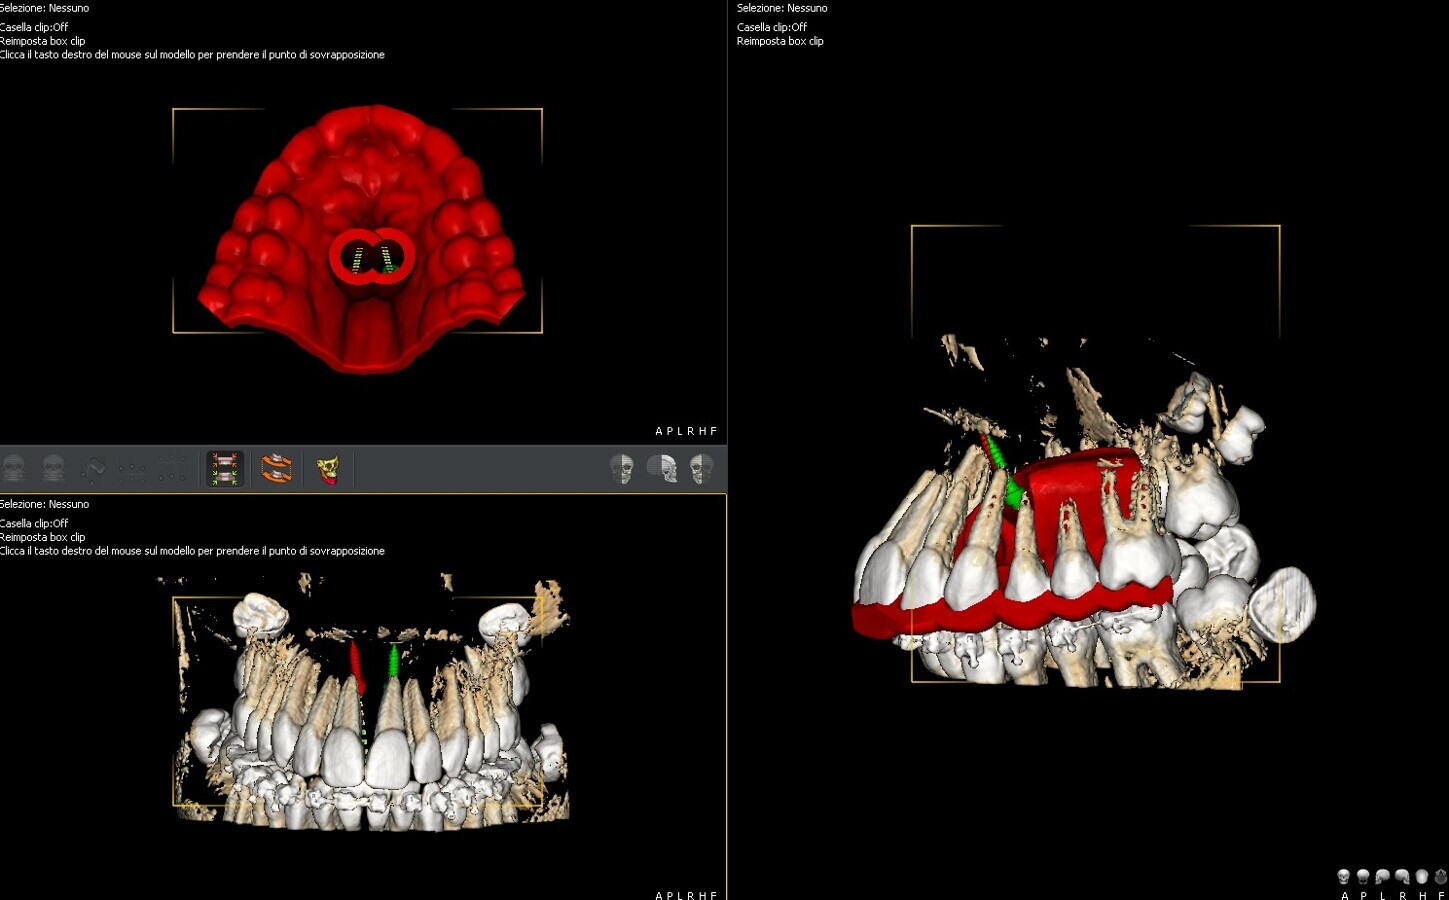

In questo stadio la fusione della sutura è già avvenuta parzialmente o totalmente, ed è quindi stata eseguito una MARPE. È stata progettata una dima CAD/CAM, mediante protocollo Easy Driver5. La CBCT è stata sovrapposta alla scansione digitale STL (standard triangulation language) dell’arcata dentale superiore, per valutare con estrema precisione il sito più adatto di inserimento, la lunghezza e il diametro delle viti, rispettando la profondità della volta palatina, e l’inclinazione di inserimento delle viti (Fig. 4).

Fig. 4_Progettazione digitale mediante protocollo Easy Driver della posizione delle miniviti ortodontiche. Mediante il software è possibile programmare sito di inserimento, profondità è inclinazione dei TADs.